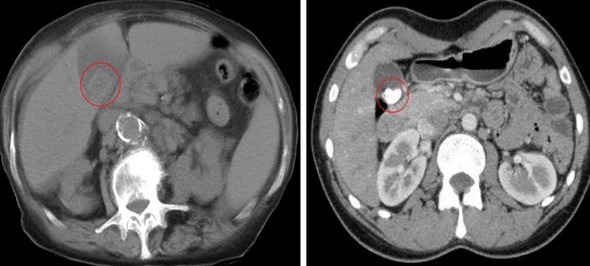

Сладж желчного пузыря на КТ

Холестериновый “мягкий” камень и плотный кальциевый конкремент на компьютерных томограммах (обведено)

Состав билиарного сладжа вариативен, литогенная желчь представляет собой субстанцию, содержащую кристаллы моногидрата холестерина, включения кальция билирубината, муцин, лизированные клетки, белковые фракции. При превалировании жестких солей в секрете обнаруживают большое количество микролитов размерами до 3-5 мм. У людей на гипокалорийной диете, при употреблении жирной пищи консистенция желчи густая за счет холестериновых включений. Описаны смешанные формы.

Сладж желчного пузыря на КТ можно предположить по косвенным признакам при наличии:

-

утолщенной стенки желчного пузыря, расширения протоковой системы;

перемещения солевого осадка и микролитов при изменении положения тела пациентом.

Кальцинированные камни в желчном пузыре — единственный тип, который можно рассмотреть на изображениях компьютерной томографии. Конкременты из чистого холестерина имеют низкую плотность. Увидеть их на снимках можно при достаточном включении кальция. Другие образования — с денситометрическими характеристиками, как и у желчи — не могут быть четко идентифицированы на КТ.